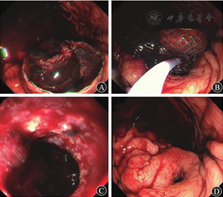

患者入院2周(恢复期)后病情较平稳。2019年10月21日,患者出现发热,体温最高达39.0 ℃,应用美罗培南(0.5 g/次,3次/d)和替加环素(50 mg/次,2次/d)抗感染治疗后,患者体温逐渐恢复至36.5 ℃。2019年10月29日复查CT示胰腺假性囊肿增大,随后患者出现中腹部胀痛、恶心等压迫症状,经多学科讨论后于11月19日行超声内镜引导下经胃胰腺假性囊肿金属支架置入术(图2),术中采集引流液进行细菌培养,等待药敏试验结果期间继续予美罗培南(0.5 g/次,3次/d)和替加环素(50 mg/次,2次/d)抗感染治疗,2019年11月21日(支架置入2 d后)常规行胃镜下经金属支架胰腺坏死组织清除术(图3),术后患者生命体征平稳。2019年11月22日凌晨4:00患者无明显诱因突发呕血,呕吐量约500 mL的鲜红色液体;排暗红色血便1次,量约150 mL;伴心悸、出冷汗,血压为80/50 mmHg,急查血常规示白细胞计数为19.65×109/L,红细胞计数为3.29×1012/L,血红蛋白为105 g/L,急诊CT检查示胰周包裹性积液和积血。急诊胃镜检查示囊肿支架内附着大量血凝块,予拔除金属支架,未见活动性出血(图4),立即行腹腔数字减影血管造影,预防胰大动脉和胰背动脉栓塞,同时予输血和止血等对症支持治疗,患者未再发生活动性出血。

图4 2019年11月22日急诊胃镜检查示胰腺囊肿内出血

A 金属支架内见血凝块 B 用圈套器拔除支架 C 胰腺窦道内无活动性出血 D 支架拔除后胃黏膜窦道处无活动性出血